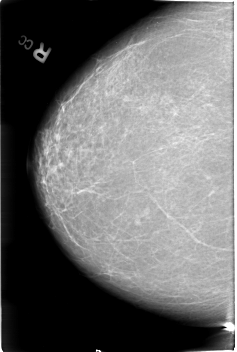

B_3018_1.LEFT_CC

FILE: B_3018_1.LEFT_CC.OVERLAY

TOTAL_ABNORMALITIES 1

ABNORMALITY 1

LESION_TYPE MASS SHAPE LOBULATED MARGINS ILL_DEFINED

ASSESSMENT 4

SUBTLETY 4

PATHOLOGY MALIGNANT

TOTAL_OUTLINES 1

BOUNDARY